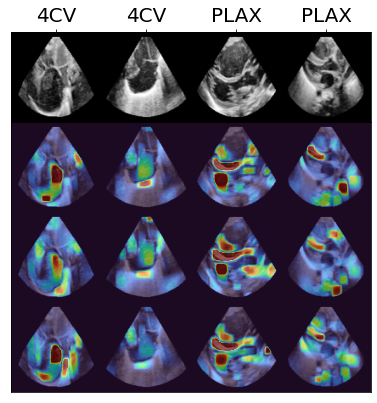

We propose a novel anomaly detection method for echocardiogram videos. The introduced method takes advantage of the periodic nature of the heart cycle to learn different variants of a variational latent trajectory model (TVAE). The models are trained on the healthy samples of an in-house dataset of infant echocardiogram videos consisting of multiple chamber views to learn a normative prior of the healthy population. During inference, maximum a posteriori (MAP) based anomaly detection is performed to detect out-of-distribution samples in our dataset. The proposed method reliably identifies severe congenital heart defects, such as Ebstein's Anomaly or Shonecomplex. Moreover, it achieves superior performance over MAP-based anomaly detection with standard variational autoencoders on the task of detecting pulmonary hypertension and right ventricular dilation. Finally, we demonstrate that the proposed method provides interpretable explanations of its output through heatmaps which highlight the regions corresponding to anomalous heart structures.